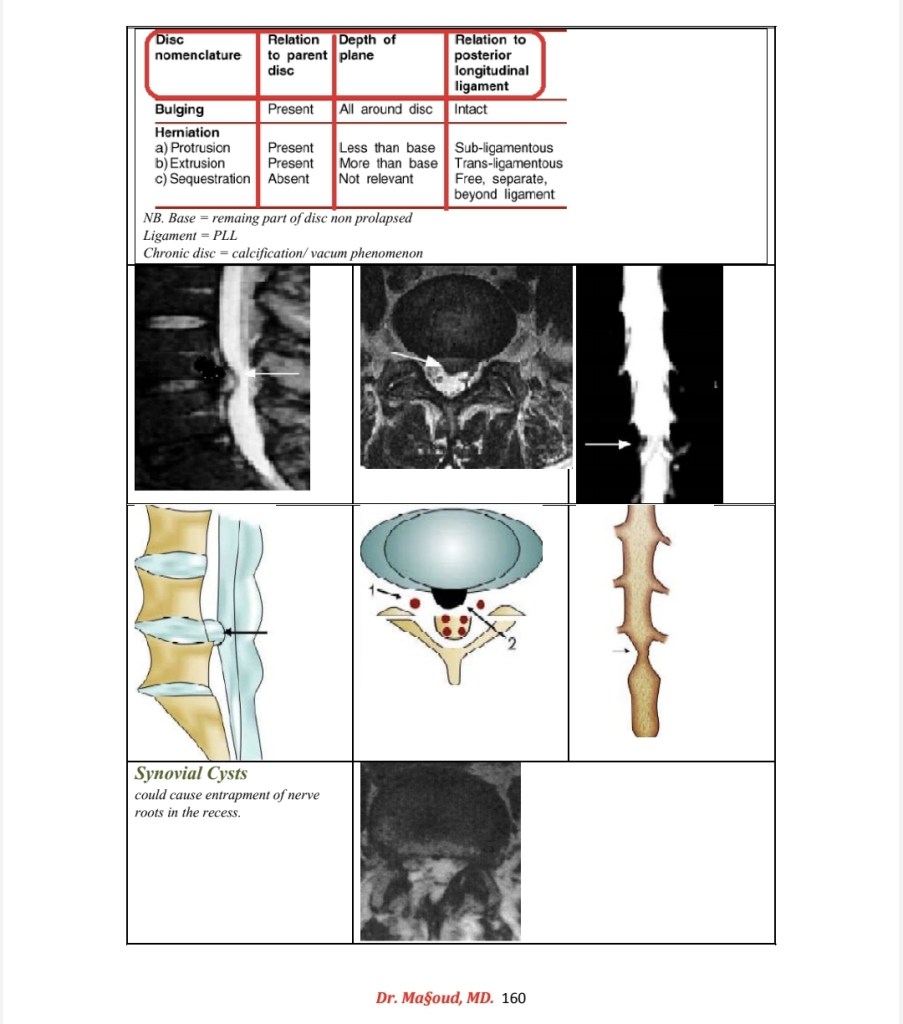

Spine imaging